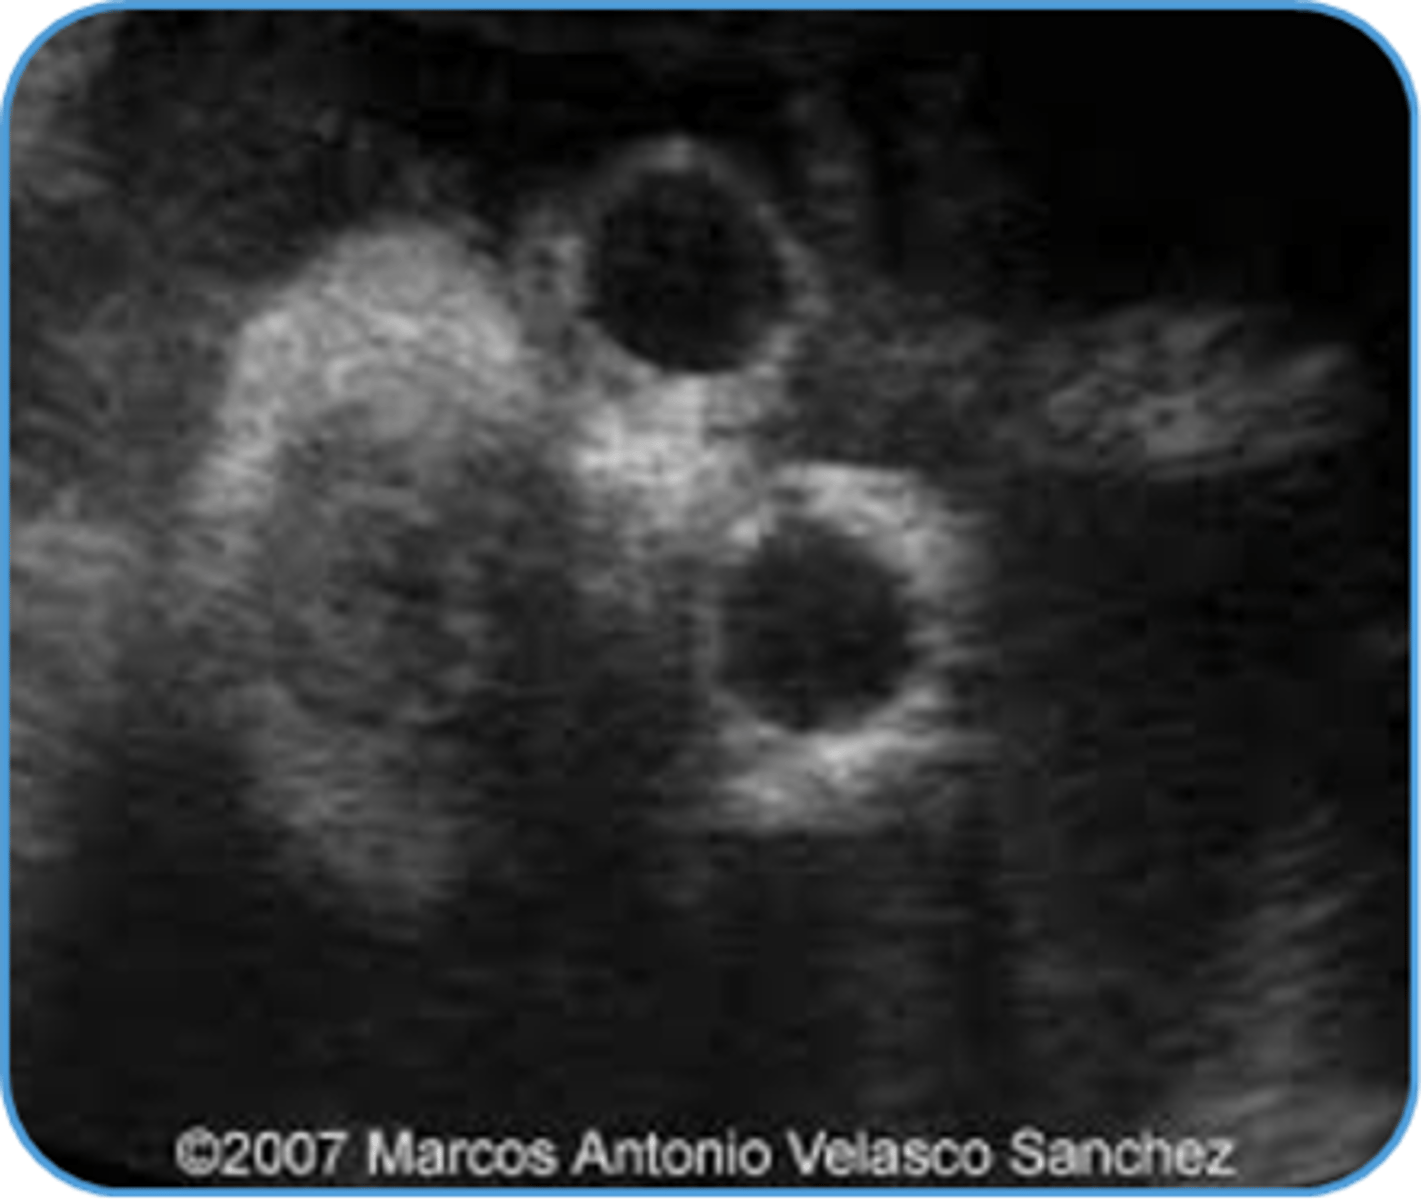

Potter's Syndrome Type II - Multicystic Dysplastic Kidney Disease

Kidney tissue is replaced by cysts - multiple and variable in size

Usually unilateral

Enlarged kidneys

Ill-defined walls & parenchyma/pelvis

Potter's Syndrome Type III - Autosomal Dominant Polycystic Kidney Disease

Bilateral large cysts

Large kidneys

Hyperechoic parenchyma

Normal bladder/fluid levels